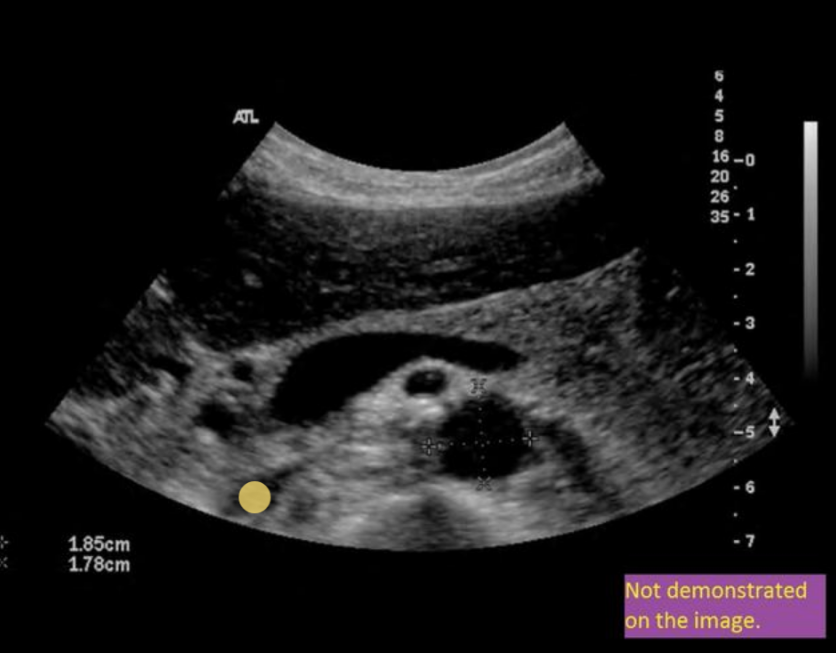

this image is

.

a) incorrect label + diameter

b) correct label; incorrect diameter

c) correct label; correct diameter

d) incorrect label; correct diameter

a. incorrect label + diameter